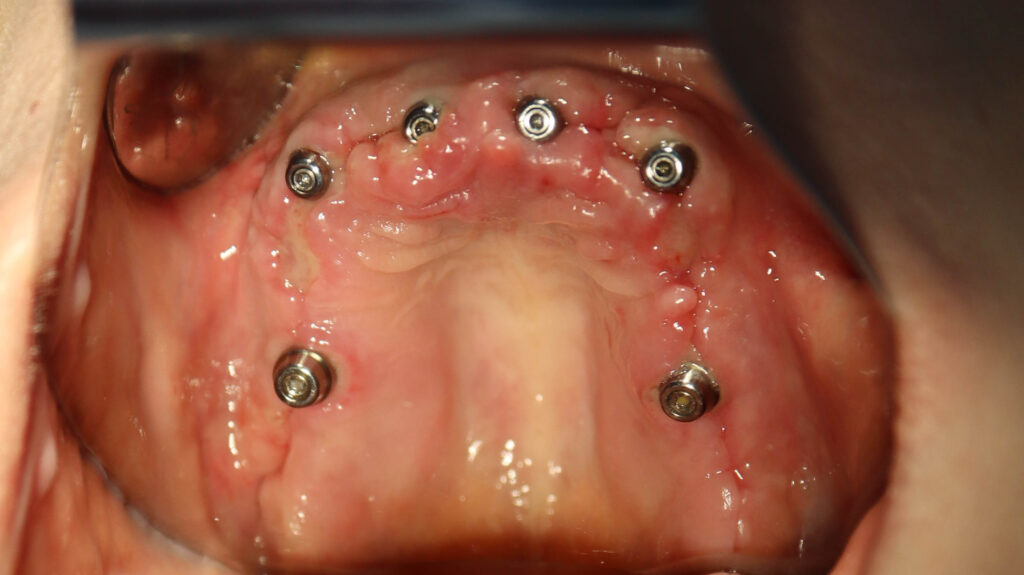

Ситуация до лечения

Пациент обратился с жалобами на эстетические недостатки.

Поставлен диагноз: частичная адентия.

Моляры на верхней челюсти отсутствуют